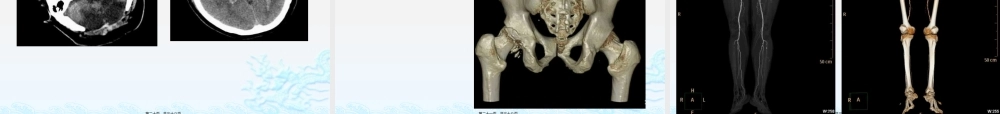

放射科科普(kēpǔ)漫谈李昌晓2018年8月6日第一页,共三十八页。一提到(tídào)放射科,老百姓就联想起几个事。。。第二页,共三十八页。哇,你们(nǐmen)放射科是个危险地带!第三页,共三十八页。找对象,别找放射科,他们那个,辐射大大的,恐怕(kǒngpà)……不能生孩子第四页,共三十八页。一病人进入(jìnrù)机房照腰椎,躺机床的时候看到他双手捂住眼睛。我问怎么了,不舒服?病人说:我怕眼睛会瞎!!!第五页,共三十八页。科普(kēpǔ)放射科包括普通(ptōng)ǔ放射科(拍片)、CT、磁共振,超声。以诊断为主要业务,也开展部分介入工作。其中拍片、CT有X线辐射,但射线量相对放疗来说低得多。MRI、超声没有辐射。放射科技师一般是隔室操作,而且照相室的门、玻璃、包括墙面都是特殊材料,屏蔽辐射的。第六页,共三十八页。第七页,共三十八页。第八页,共三十八页。放射科的部门(bùmén)凌晨2点,以前拍片、CT值班室的门相对,“病人敲门,大夫(dàfū)”“”,我拍片,对门!“大夫,我做CT”“”,对门!“……”大夫,我不知道是做啥第九页,共三十八页。一熟人来医院找我取物品,“熟人:我在肿瘤科,三楼,你在几楼啊,”我“:肿瘤科门诊往东走,看见放射科拍片室CT室的牌子(páizi)了吗?”熟人:没有……啊,我问问,没人知道噢,你们不在肿瘤科病房这吗?我到了放疗科!第十页,共三十八页。科普:大放射科包括普通放射科(拍片、钡餐(bèicān)透视)、CT、磁共振、介入及超声。放疗属于肿瘤科第十一页,共三十八页。第十二页,共三十八页。第十三页,共三十八页。病人拿着片子过来问:医生你们这里的CT图片怎么没有彩色啊?另一个家属附和:“小医院的机子没那么好的,一般都是黑白(hēibái)”的科普:平片、CT、MRI的图像一般是灰阶成像,就是黑白图像。彩超的彩色是以不同颜色显示血流的方向,色泽的深浅代表血流的流速。原理不同,并非不够高级第十四页,共三十八页。第十五页,共三十八页。技师(jìshī)与医师与很多人交谈,得知我是放射科医生,都会问,我之前到你们医院放射科做检查怎么没见过你?科普:影像科医生分两部分,一部分是技师,就是操作(cāozuò)机器,拍片,做CT;一部分是执业医师,在校学习的是临床+影像诊断,执医考试、职称晋升等各方面与临床医师是一样的,他们的工作是书写诊断报告,为病人的诊断和治疗提供有力信息超声科一般是技师+医师第十六页,共三十...

0下载